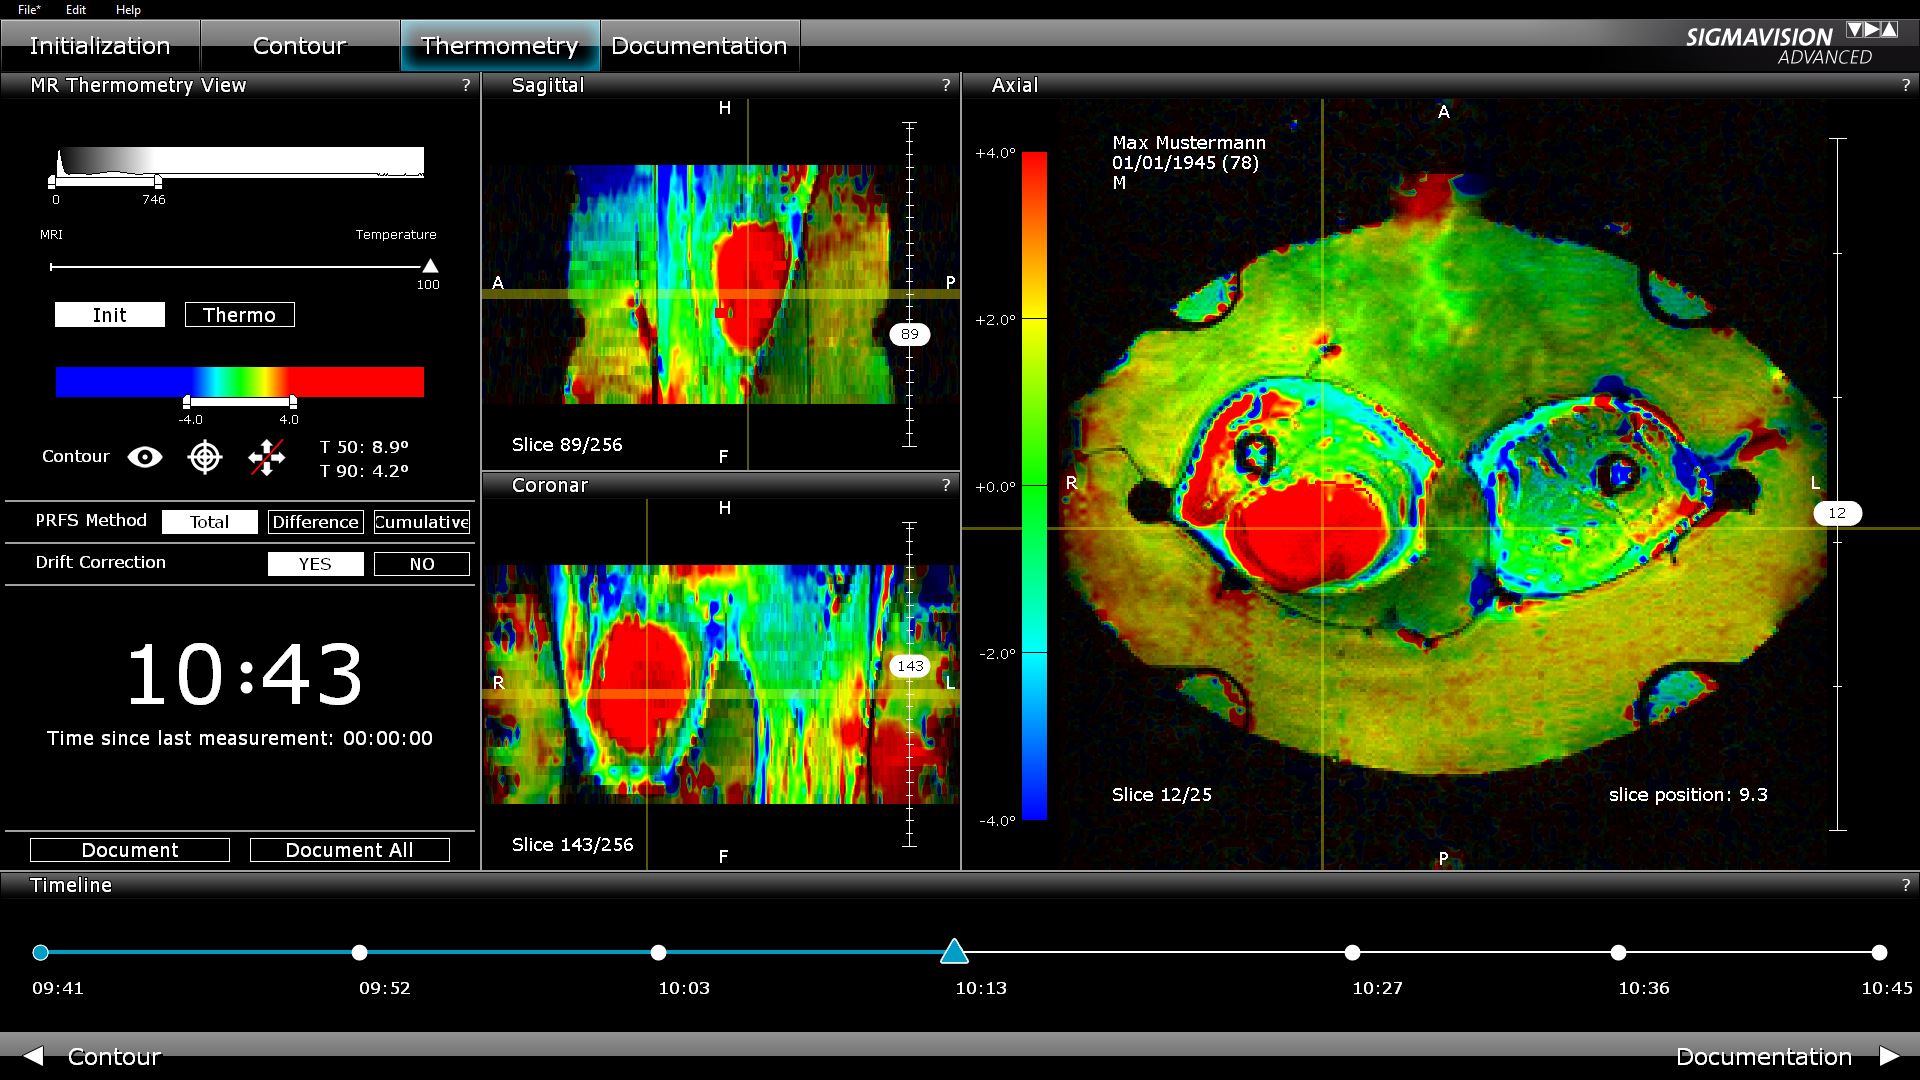

Non-invasive Temperature Monitoring during the treatment

This menu point allows for the calculation and visualization of the axial thermal images. Following each new MRI measurement, the user is supplied with the calculated, color-coded 3D temperature images.

During treatment, the MR-image-guided hyperthermia records the MR volume at regular intervals – e g every 5 minutes – and color-coded regions represent the calculated thermal image on the resulting axial slices. The temporal progression of the temperature changes in the tumor and muscle tissue can be reconstructed via the timeline. The user can react to unexpected and undesired heating (hot spots) during the treatment.

SIGMAVISION ADVANCED represents a highly professional tool for the recording of heat changes in the patient during the treatment.